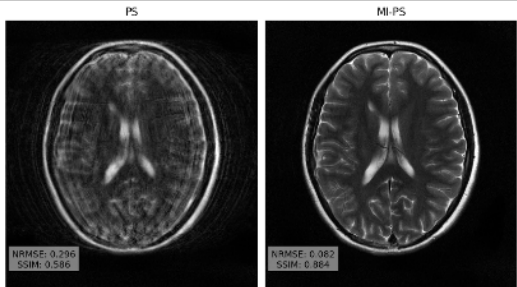

Brett Levac, Ajil Jalal, Kannan Ramchandran, Jon Tamir

57th Asilomar Conference on Signals, Systems, and Computers 2023

Magnetic resonance imaging (MRI) exam protocols consist of multiple contrast-weighted images of the same anatomy to emphasize different tissue properties. Due to the long acquisition times required to collect fully sampled k-space measurements, it is common to only collect a fraction of k-space for each scan and subsequently solve independent inverse problems for each image contrast. Recently, there has been a push to further accelerate MRI exams using data-driven priors, and generative models in particular, to regularize the ill-posed inverse problem of image reconstruction. These methods have shown promising improvements over classical methods. However, many of the approaches neglect the additional information present in a clinical MRI exam like the multi-contrast nature of the data and treat each scan as an independent reconstruction. In this work we show that by learning a joint Bayesian prior over multi-contrast data with a score-based generative model we are able to leverage the underlying structure between random variables related to a given imaging problem. This leads to an improvement in image reconstruction fidelity over generative models that rely only on a marginal prior over the image contrast of interest.